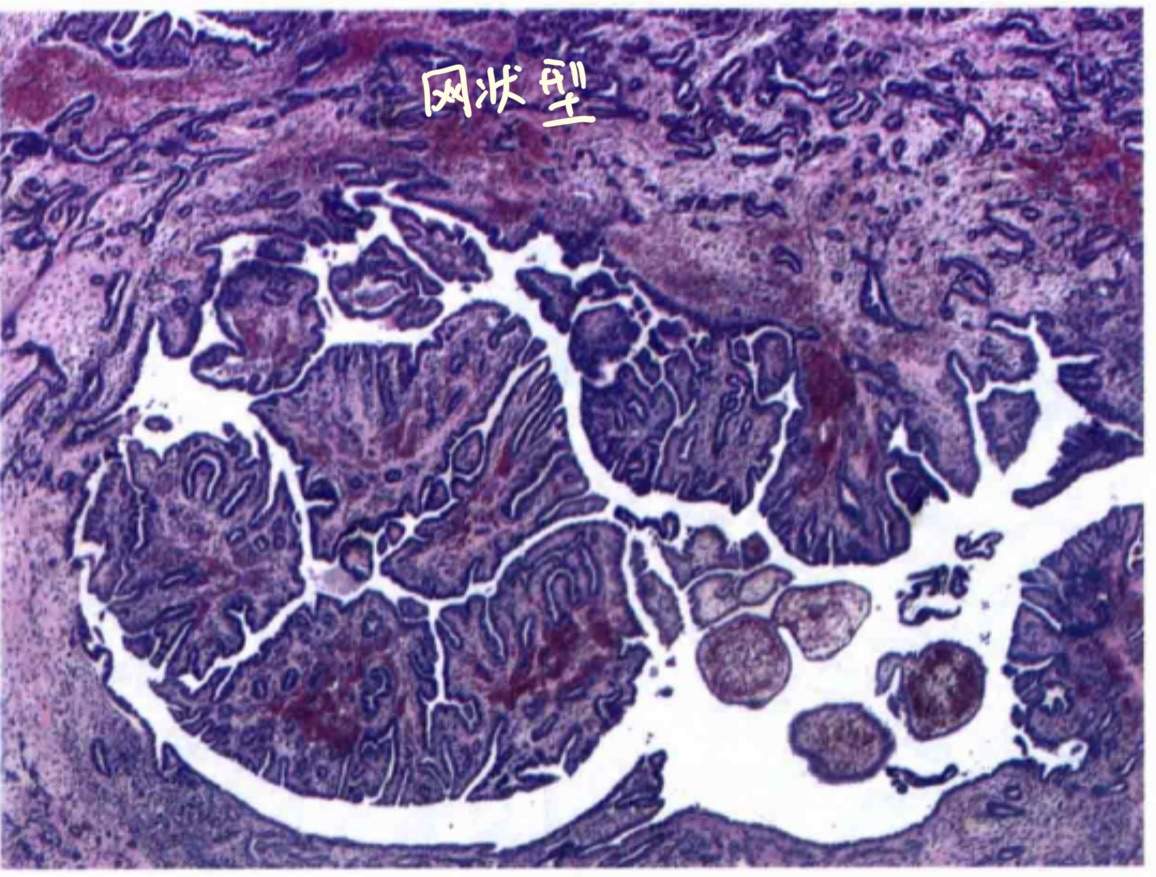

最后,它有个特殊类型:网状型Sertoli-Leydig细胞肿瘤,如图:

不规则分枝状,细长,狭窄,常呈裂隙样。